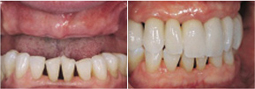

利用4颗种植体,于两颗前牙部位的种植体垂直植入牙槽骨内,而两颗中远部位的种植体采取倾斜角度植入牙槽骨内,然后在种植体的基台上安装拱形连桥牙冠,从而实现半口缺失牙完美修复